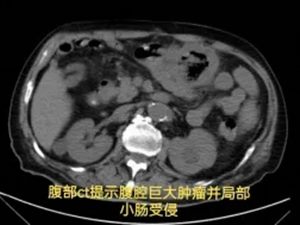

胃肠·甲状腺外科罗昭锋副主任医师会诊后,结合患者手术史与影像学检查,作出关键判断:结肠肿瘤复发并活动性出血——此时,可能只有外科手术才能扭转乾坤。

经积极输血、肠镜证实诊断后,患者转入胃肠·甲状腺外科接受手术治疗。术中探查到如同"炸弹"一样的巨大肿瘤。经仔细"拆弹",团队完整切除了出血部位的复发肿瘤,以及被侵犯的3处小肠。

困扰患者一个月的持续便血,终于停止了。因失血导致的苍白与心悸,被红润的面色和安稳的心跳所取代。出院后,家属特意为胃肠·甲状腺外科团队送来了感谢信与牌匾。